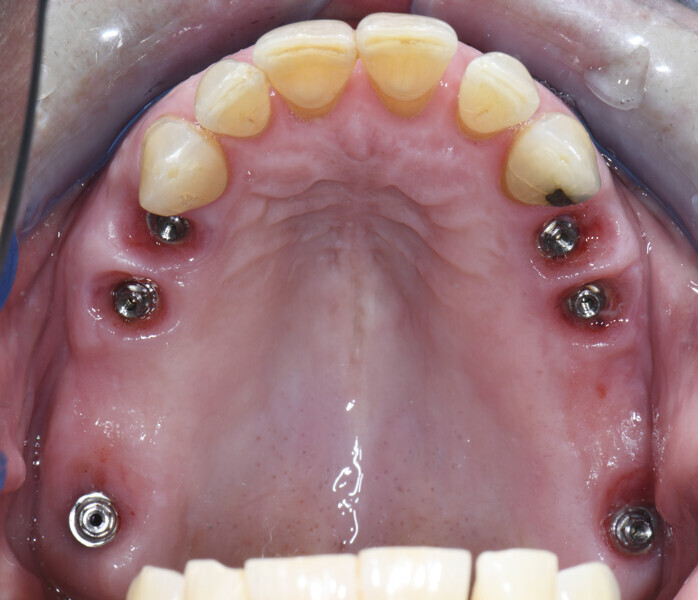

All files were imported into Atlantis Scan Upload for ordering of the Atlantis BridgeBase frameworks (Dentsply Sirona; Fig. 12). After approval of the Atlantis BridgeBase and core file designs, the Atlantis BridgeBase frameworks and zirconia shells were manufactured (Figs. 13–16).

After a clinical try-in, the Atlantis BridgeBase frameworks were cemented to the zirconia shells and delivered to the patient (Figs. 17 & 18).